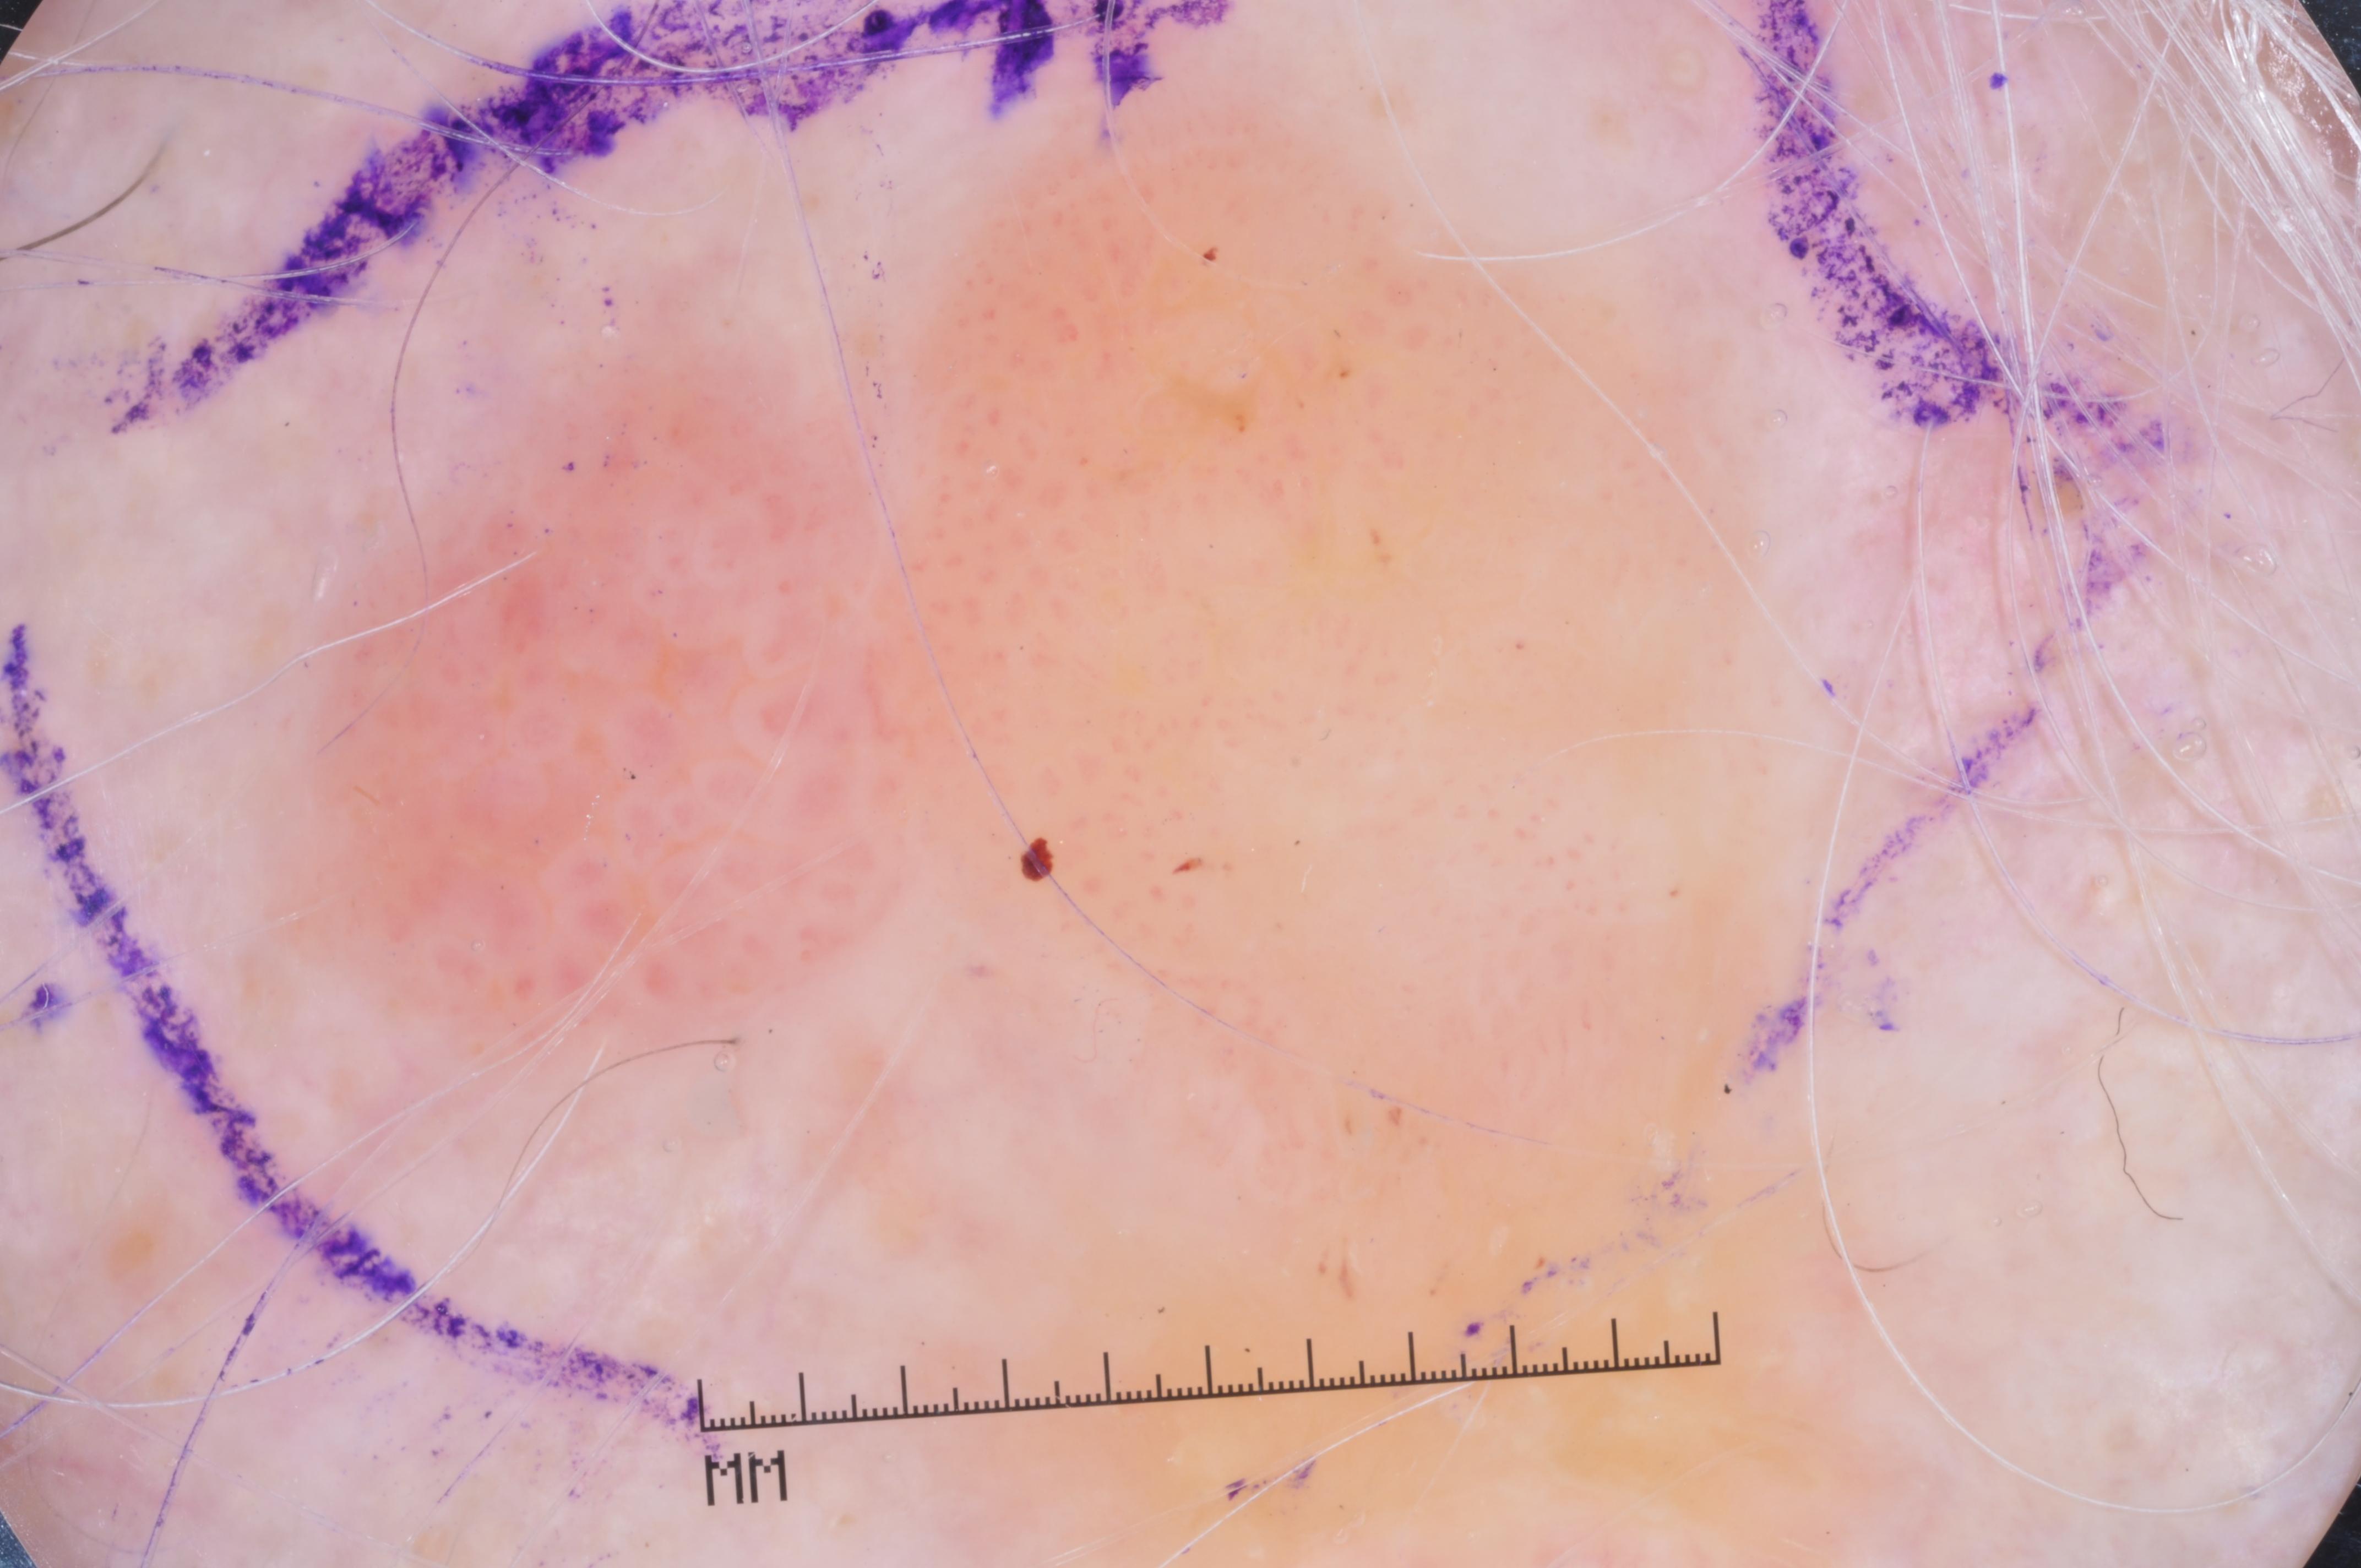

{

"age_approx": 65,

"anatom_site_general": "upper extremity",

"concomitant_biopsy": true,

"dermoscopic_type": "contact non-polarized",

"diagnosis_1": "Malignant",

"diagnosis_2": "Malignant melanocytic proliferations (Melanoma)",

"diagnosis_3": "Melanoma Invasive",

"diagnosis_4": "Melanoma Invasive, Associated with a nevus",

"diagnosis_confirm_type": "histopathology",

"image_type": "dermoscopic",

"lesion_id": "IL_6937786",

"melanocytic": true,

"sex": "male"

}